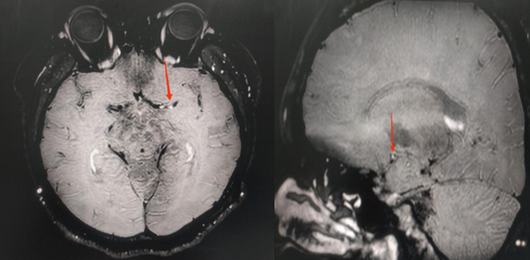

患者右侧大脑中动脉闭塞,左侧大脑中动脉M1段狭窄

高分辨磁共振血管壁成像(HR-VWI)显示血管壁明显强化斑块